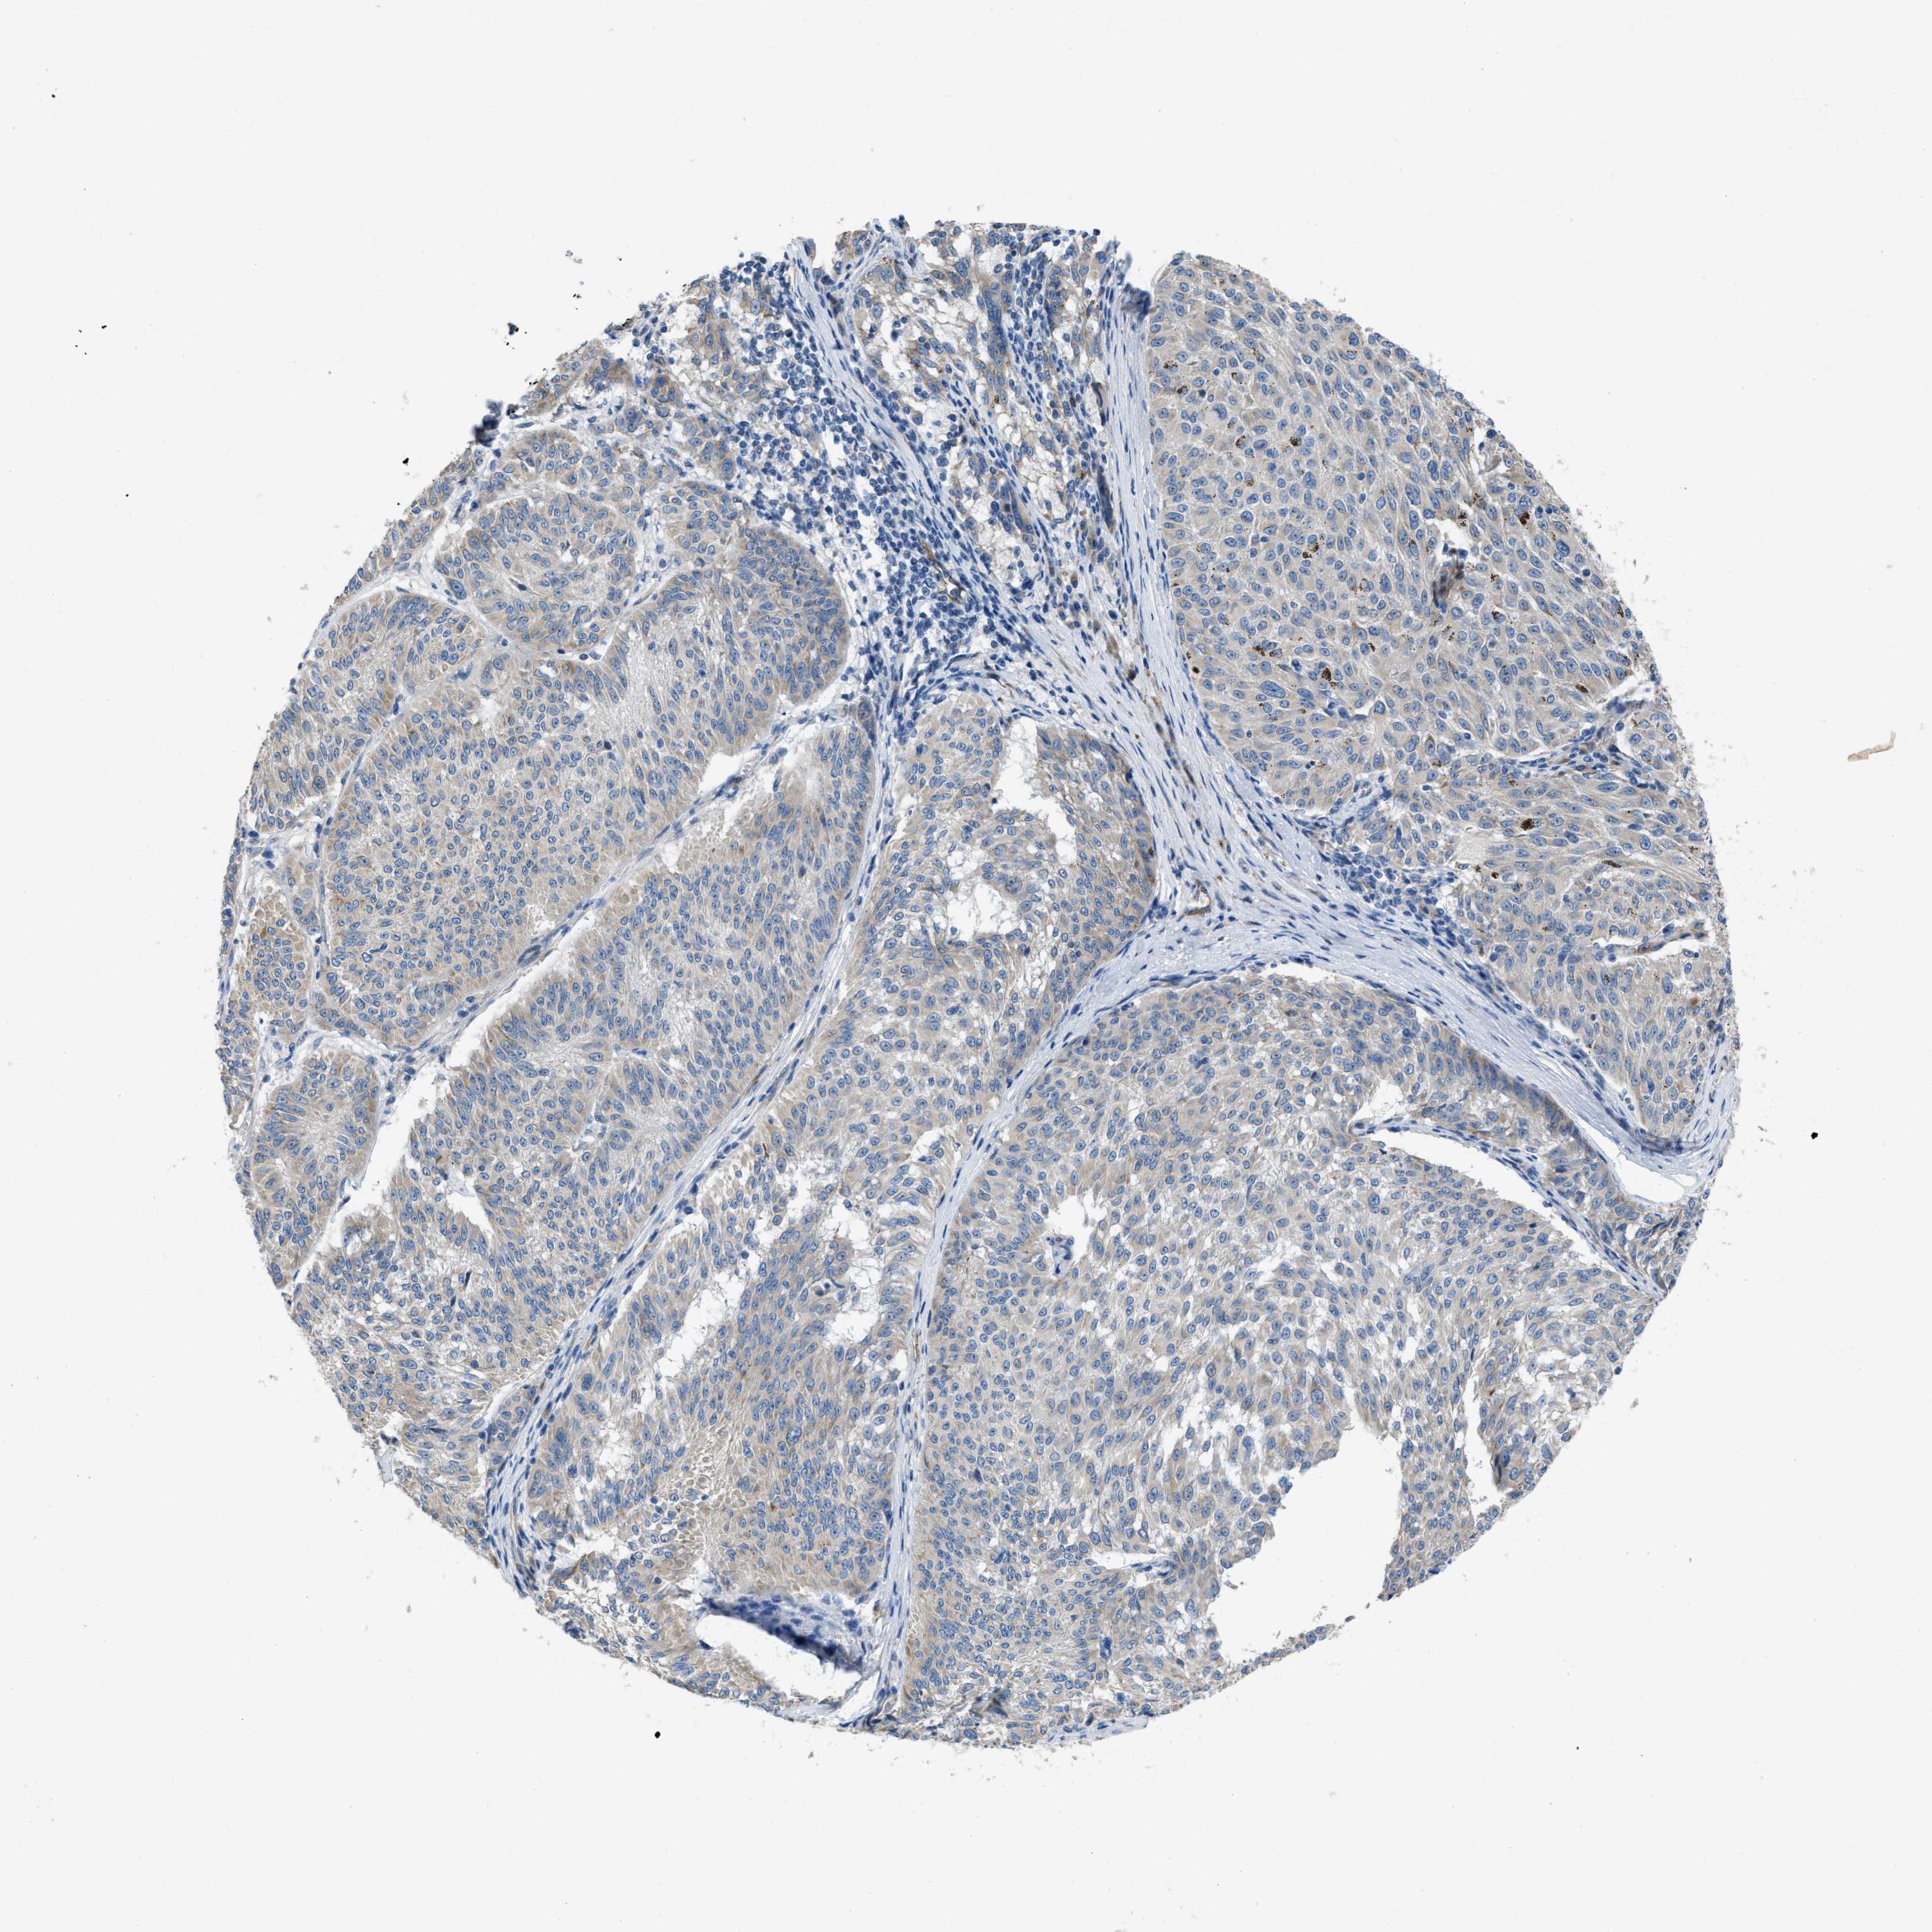

MELANOMA - Protein expressioni

A mouse-over function shows sample information and annotation data. Click on an image to view it in a full screen mode. Samples can be filtered based on level of antibody staining by selecting one or several of the following categories: high, medium, low and not detected. The assay and annotation is described here.

Note that samples used for immunohistochemistry by the Human Protein Atlas do not correspond to samples in the TCGA dataset.

Antibody stainingi

Antibody staining in the annotated cell types in the current human tissue is reported as not detected, low, medium, or high, based on conventional immunohistochemistry profiling in selected tissues. This score is based on the combination of the staining intensity and fraction of stained cells.

Each image is clickable and will lead to virtual microscopy that enables deeper exploration of all samples and also displays staining intensity scores, fraction scores and subcellular localization as well as patient and tissue information for each sample.

Antibody HPA018284

Staining

High

Medium

Low

Not detected

Intensity

Strong

Moderate

Weak

Negative

Quantity

>75%

75%-25%

<25%

None

Location

Nuclear

Cytoplasmic/membranous

Cytoplasmic/membranous,nuclear

Malignant melanoma, NOS

Malignant melanoma, Metastatic site